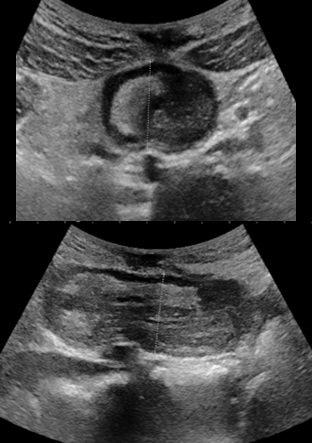

An hour later in the emergency room there is no more pain, a new ultrasound is requested which does not found the intussusception. He discharges and an appointment was set for him in three months in the event of no recurrence. The patient was seen again on the scheduled date and there was no recurrence or sign of complication. Seventeen months later from the first episode of invagination, the patient consults to the emergency room for episodes of severe abdominal pain localized in the epigastric region, of high intensity, without signs of irradiation and similar to those of the previous attack, no transit since two days (usual, consistent with his chronic constipation). The general condition of the patient is preserved, temperature at 36.4°C, pulse: 90 per minute, SaO2 : 100%, weight: 57.7 kg, digital pain assessment: 8, spontaneous ventilation ambient air: 18 cycles per minute, pale coloring, nauseous, but no vomiting. Physical examination revealed epigastric pain, a numb, helpless, unbloated abdomen, no palpable organomegaly. Ultrasound performed in an emergency found ileum intussusception at the epigastric location with the presence of a probable fatty structure mimiking to a mesenteric fat or a lipoma, a few visible common mesenteric lymph nodes, no coeliomesenteric or retroperitoneal adenopathy, there is no intra-abdominal fluid effusion (Figure 2).